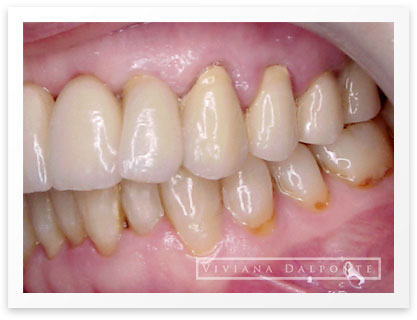

CASO 6: Restauración con prótesis fija en ambos maxilares